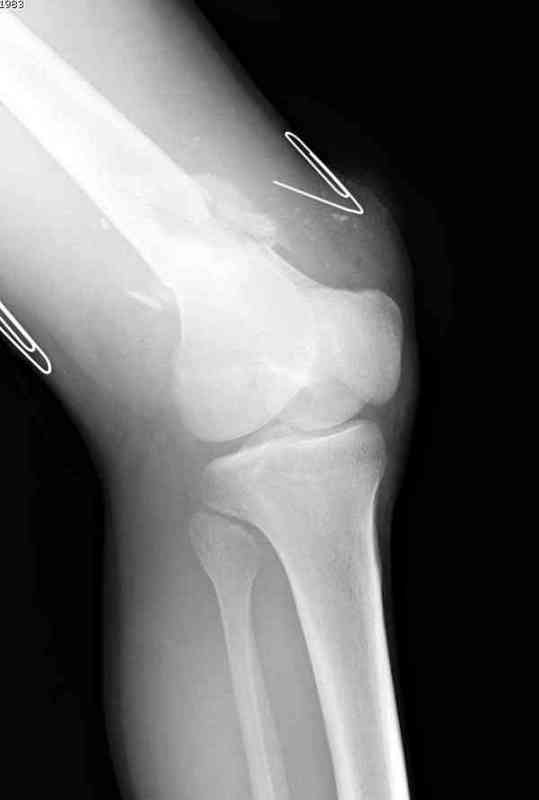

Огнестрельный перелом бедра

Вдогонку к обсуждению случая несращения дистального отдела бедра 9 мая утром поступил больной с огнестрельной раной, осмотрен сосудистым специалистом, сделана ангиограмма (снимки)

Во время операции при вскрытии обнаружили кровотечение, рану забили салфетками, установили пластину locking DePuy.

Из-за возрастающего давления в компартменте сделана фасциотомия и вызванный сосудистый хирург ушил разрыв вены на уровне перелома. Все раны оставлены открытими, в пятницу закроем.